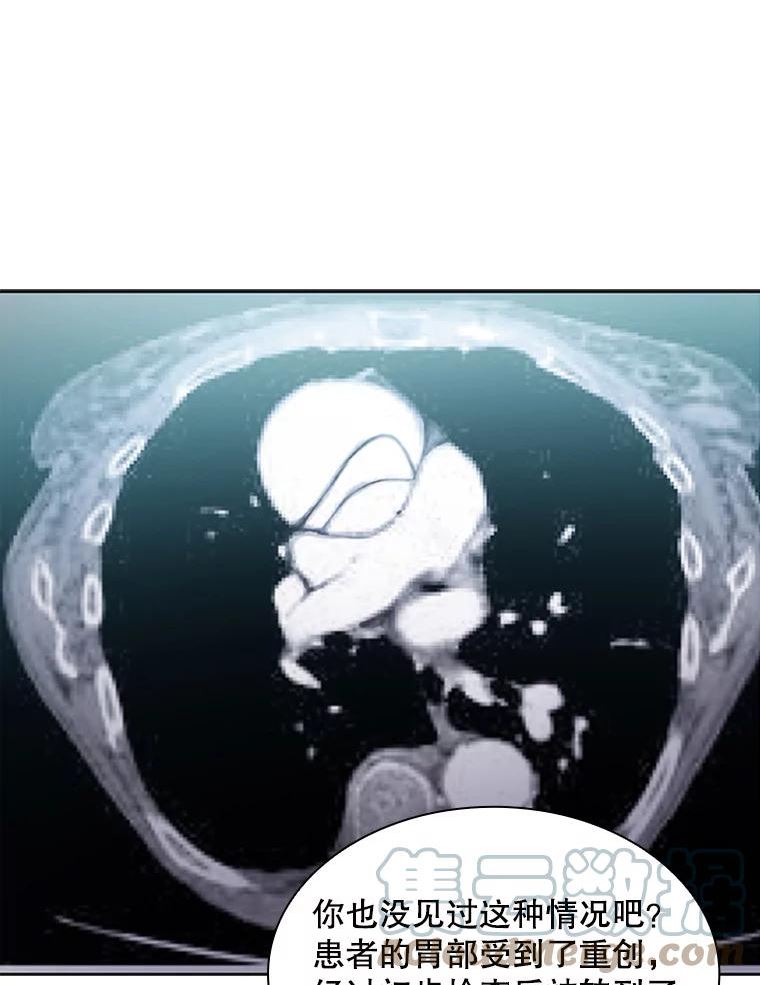

医生崔泰秀

111.暂时休息

奇幻

人气 17307

简介崔泰秀本是医院里最底层的实习医生,却因为意外挽救了世界顶级外科医生的性命,而获得了他全部的医学知识,天才医生的细胞蔓延身体的每个角落,他的命运从此改变!